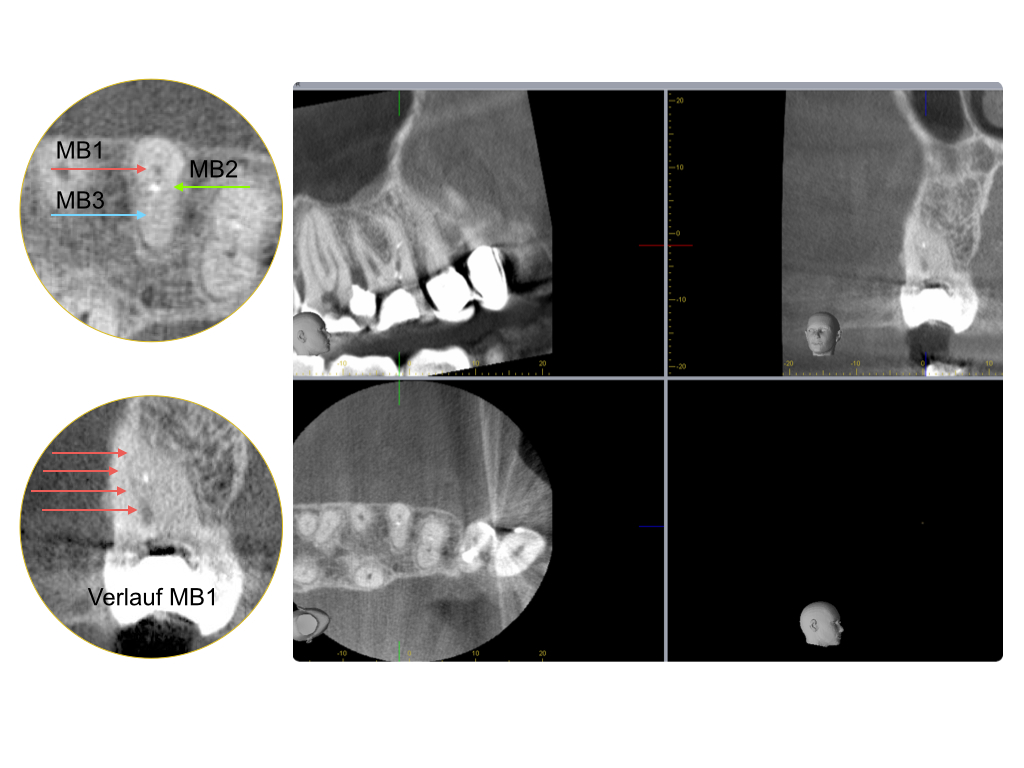

Instrumentenfrakturen (2)